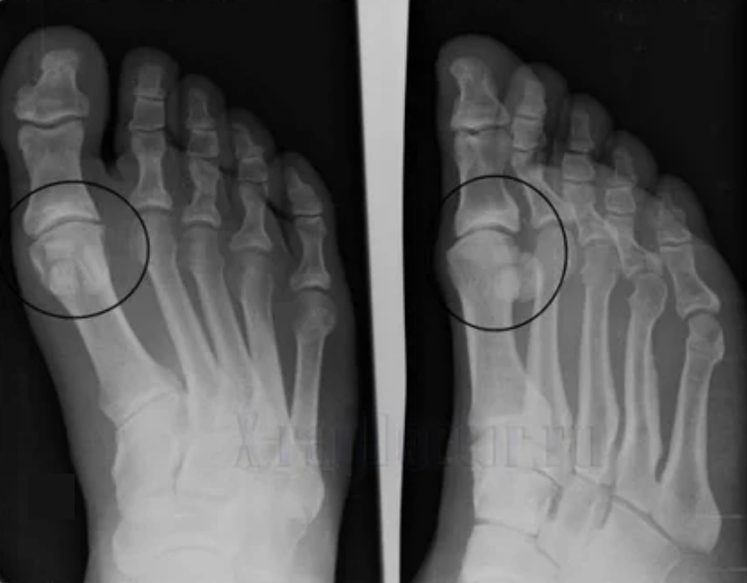

- Réduire l'écart dans l'écart de l'articulation, qui devient perceptible dans l'image. Le stade de la violation est déterminé par le diagnostic-tantgénologiste. Le patient ressent la complexité ou l'incapacité de redresser et de plier complètement le membre;

Diagnostic d'arthrose

Pour poser un diagnostic, les rhumatologues étudient les plaintes du patient et prescrivent un examen x-raffinement. Le plus souvent, la radiographie est utilisée dans 2 projections. Le médecin examine la présence de troubles dystrophiques dans le cartilage hyalin et les articulations osseuses. Si l'espace articulaire est réduit, les os sont déformés ou aplatis, il existe des formations kystiques à la surface du cartilage, les ostéophytes sont des signes d'arthrose évidents. Pendant l'inspection, l'arthrose indique l'instabilité de l'articulation: l'axe des membres et la subluxation est perturbé.

Souvent, une image X-Ray n'est pas en mesure de fournir des informations complètes sur l'état de l'articulation. Pour une étude plus approfondie, la tomodensitométrie est prescrite, il est efficace pour examiner les os. L'IRM est plus souvent utilisée pour étudier les tissus mous.